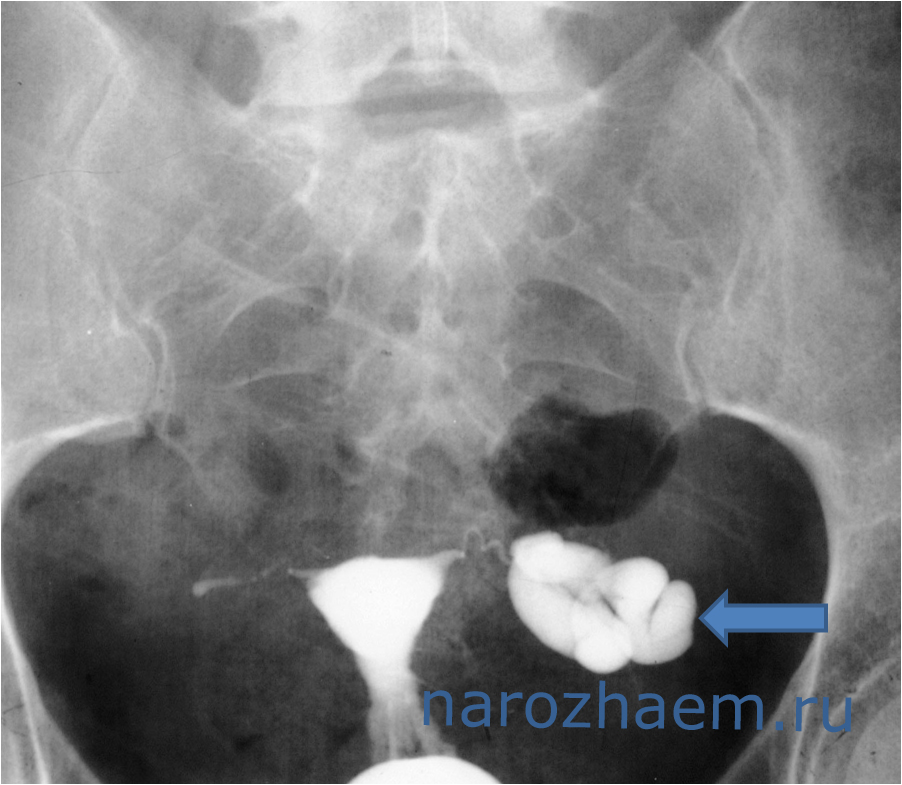

Диагностировать гидросальпинкс можно с помощью УЗИ

Патология не всегда поддаётся диагностике. При простом осмотре врач сможет заметить недуг только в запущенном состояние. Гинеколог назначает ультразвуковое исследование, рентген трубчатого органа. УЗИ покажет, есть ли жидкость, а ГСГ определит уровень непроходимости. Лапароскопия – один из методов лечения и обследования гидросальпинкса.